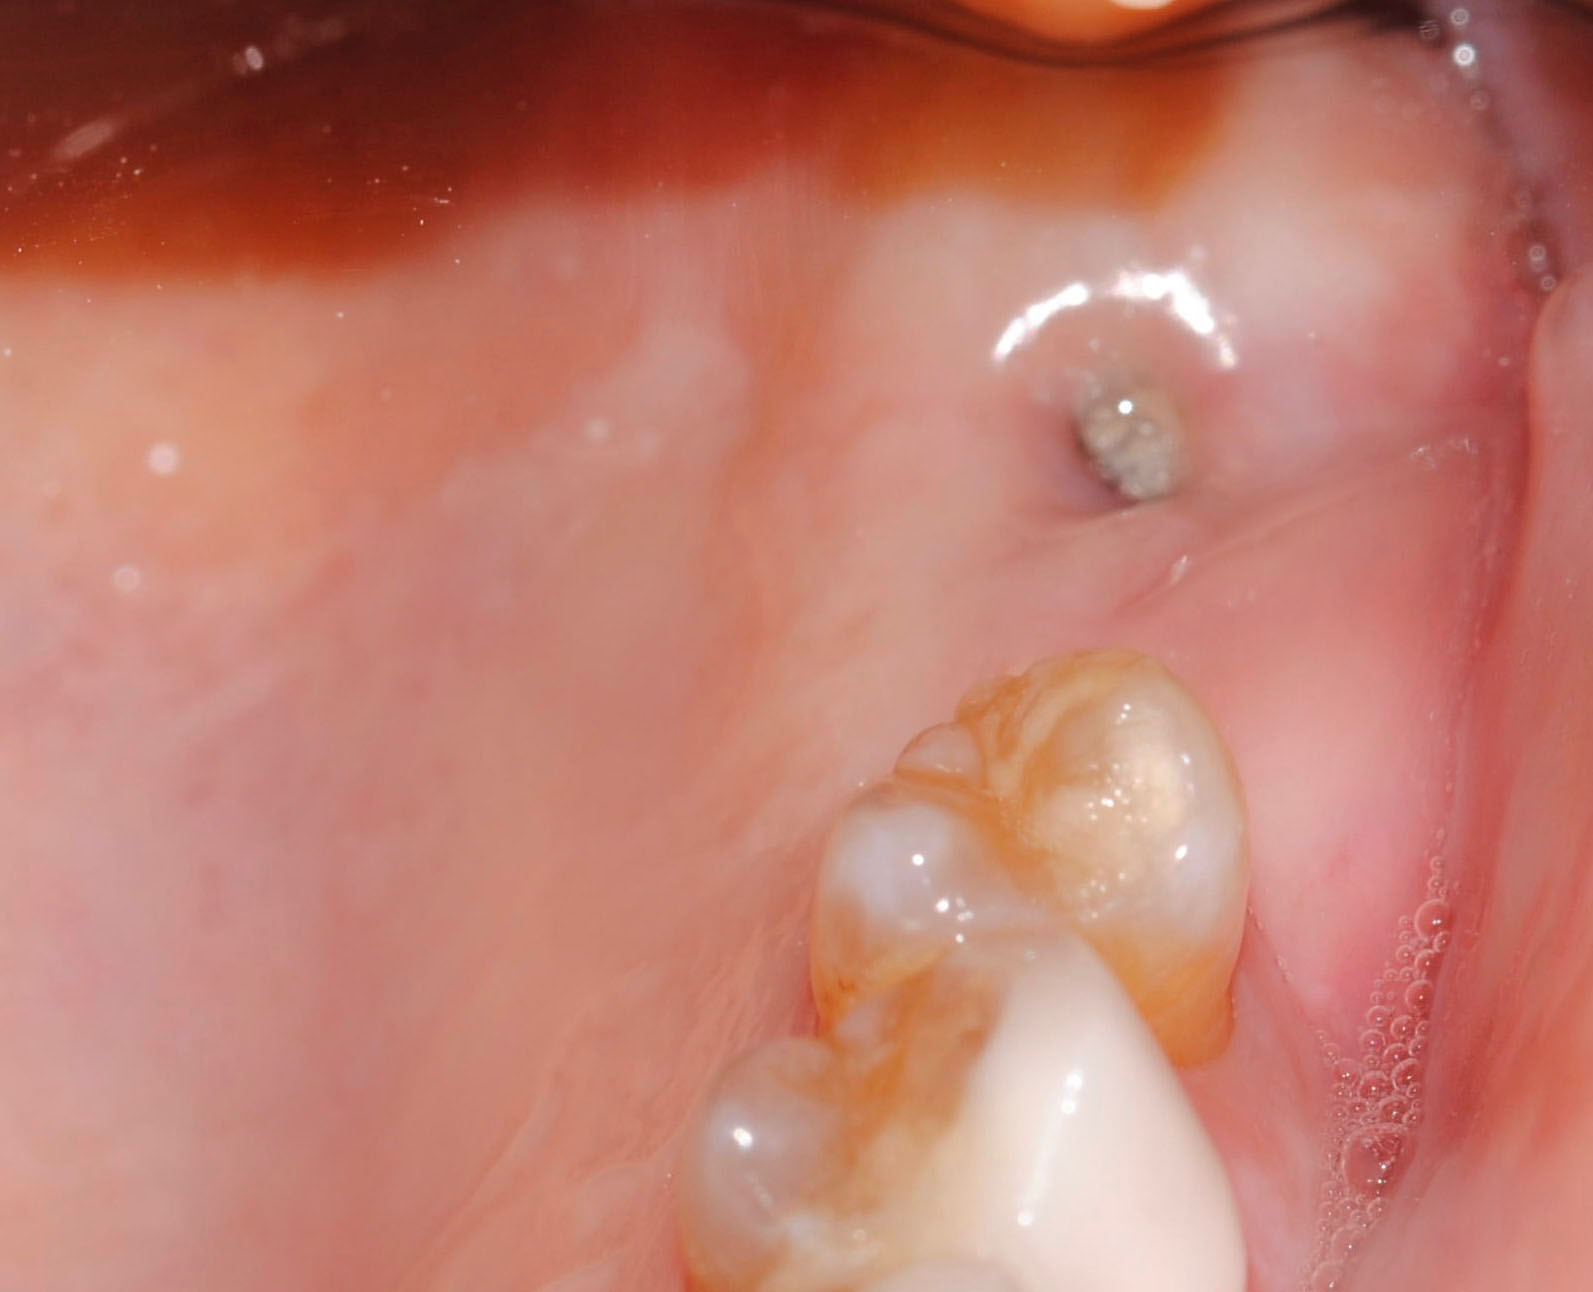

Esta es la imagen realizada durante la cirugía:

- Mediante cirugía de acceso, se eliminó restos de biomaterial y tejido fibrosado que no estaban integrados y fistuilizaban la mucosa, presentando molestias e inflamación.

- Colocación de injerto gingival libre de paladar y desplazamiento apical del colgajo, para aumentar también el vestíbulo.